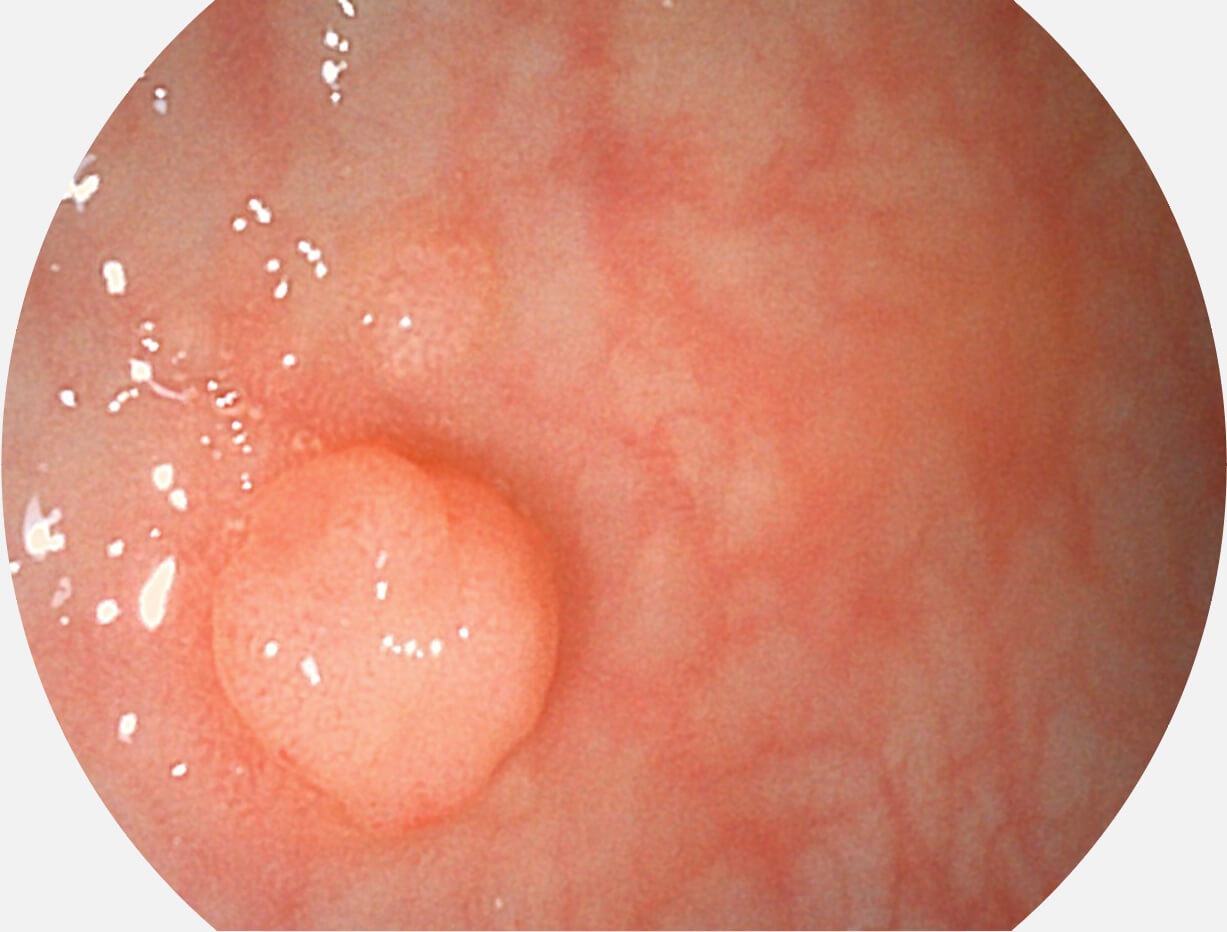

图像具有高亮度、高黏膜血管颜色对比度的特点,且不改变粘液、食物残渣、粪便的基本颜色,可在中远景下进行观察,助力消化道早期疾病的诊断。

SFI图像

白光图像